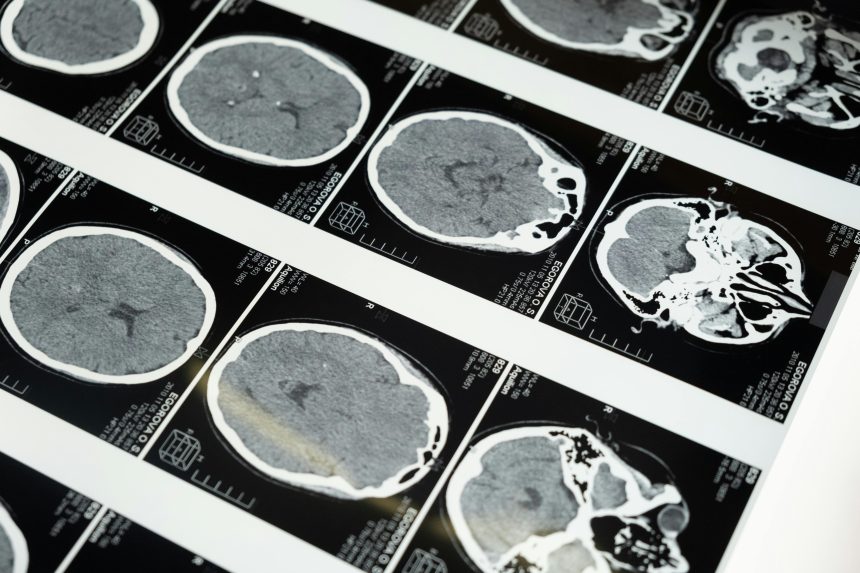

Imaging Tests

Imaging is one of the most important diagnostic tools in brain injury care.

- CT Scan (Computed Tomography): The first-line scan in emergencies. CTs quickly reveal fractures, bleeding, swelling, and blood clots.

- MRI (Magnetic Resonance Imaging): Provides more detailed images of brain tissue, useful for detecting subtle damage, diffuse axonal injury, or long-term changes.